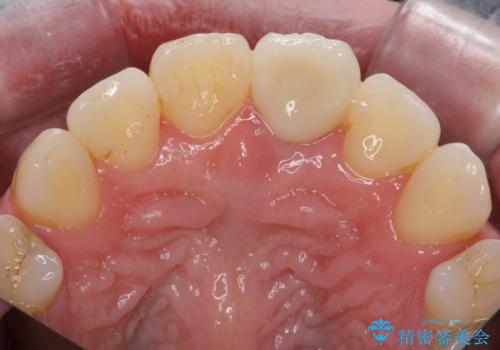

- 神経の治療をしたまま放置していた歯が、変色してきたので改善したい。と前歯の審美性の改善を求めて来院されました。

根管治療後の歯には部分的な修復処置が為され、変色が進行している状態でした。

ジルコニアクラウンを用いて、自然な色調となるよう治療を計画します。

根管治療は行わず、仮歯・ジルコニアクラウンのみの処置を行い自然な歯に仕上げることができました。